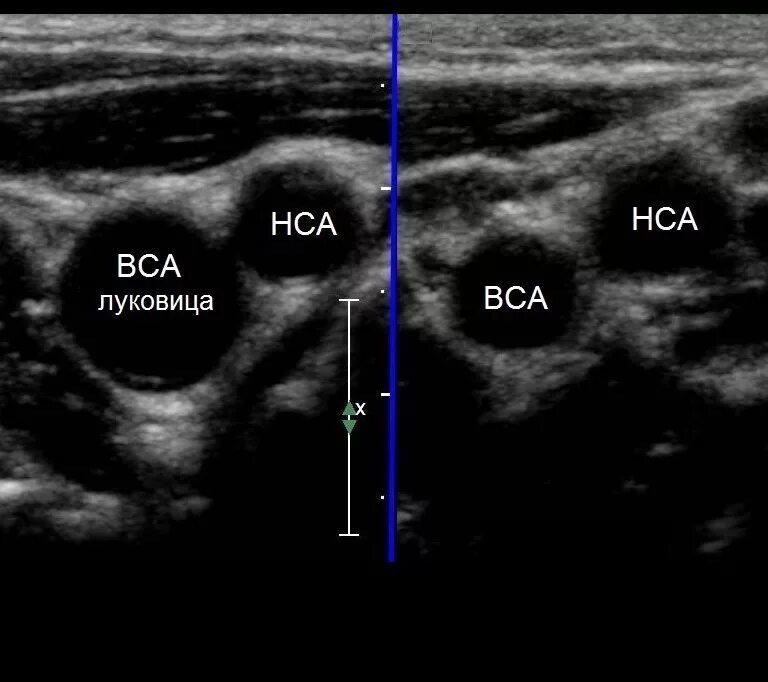

Сделать узи сонной артерии